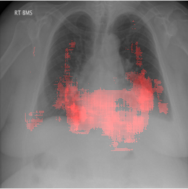

In order to test the effectiveness of the localization procedure in areas other than the heart region, we chose pulmonary edema which occurs in the lung region. Also, pulmonary edema is detected by the net like white structure in the lung area. No anatomical shape change is associated with the abnormality. We have found that the localization is obtained best when the ROIs of lungs are taken to compute the map. Following the scheme in section 3.4, localization experiment on pulmonary edema is performed as shown in Fig. 8. It has been observed that the classifier is not sensitive to the fine features like septal or Kerley B lines. The localization is mainly obtained in the lung region where excess fluid is observed. Some localization regions are outside the lung region which occurs primarily for the fact that, even though the occlusion center is outside the lung, it occludes lung region and thus the probability drop occurs.